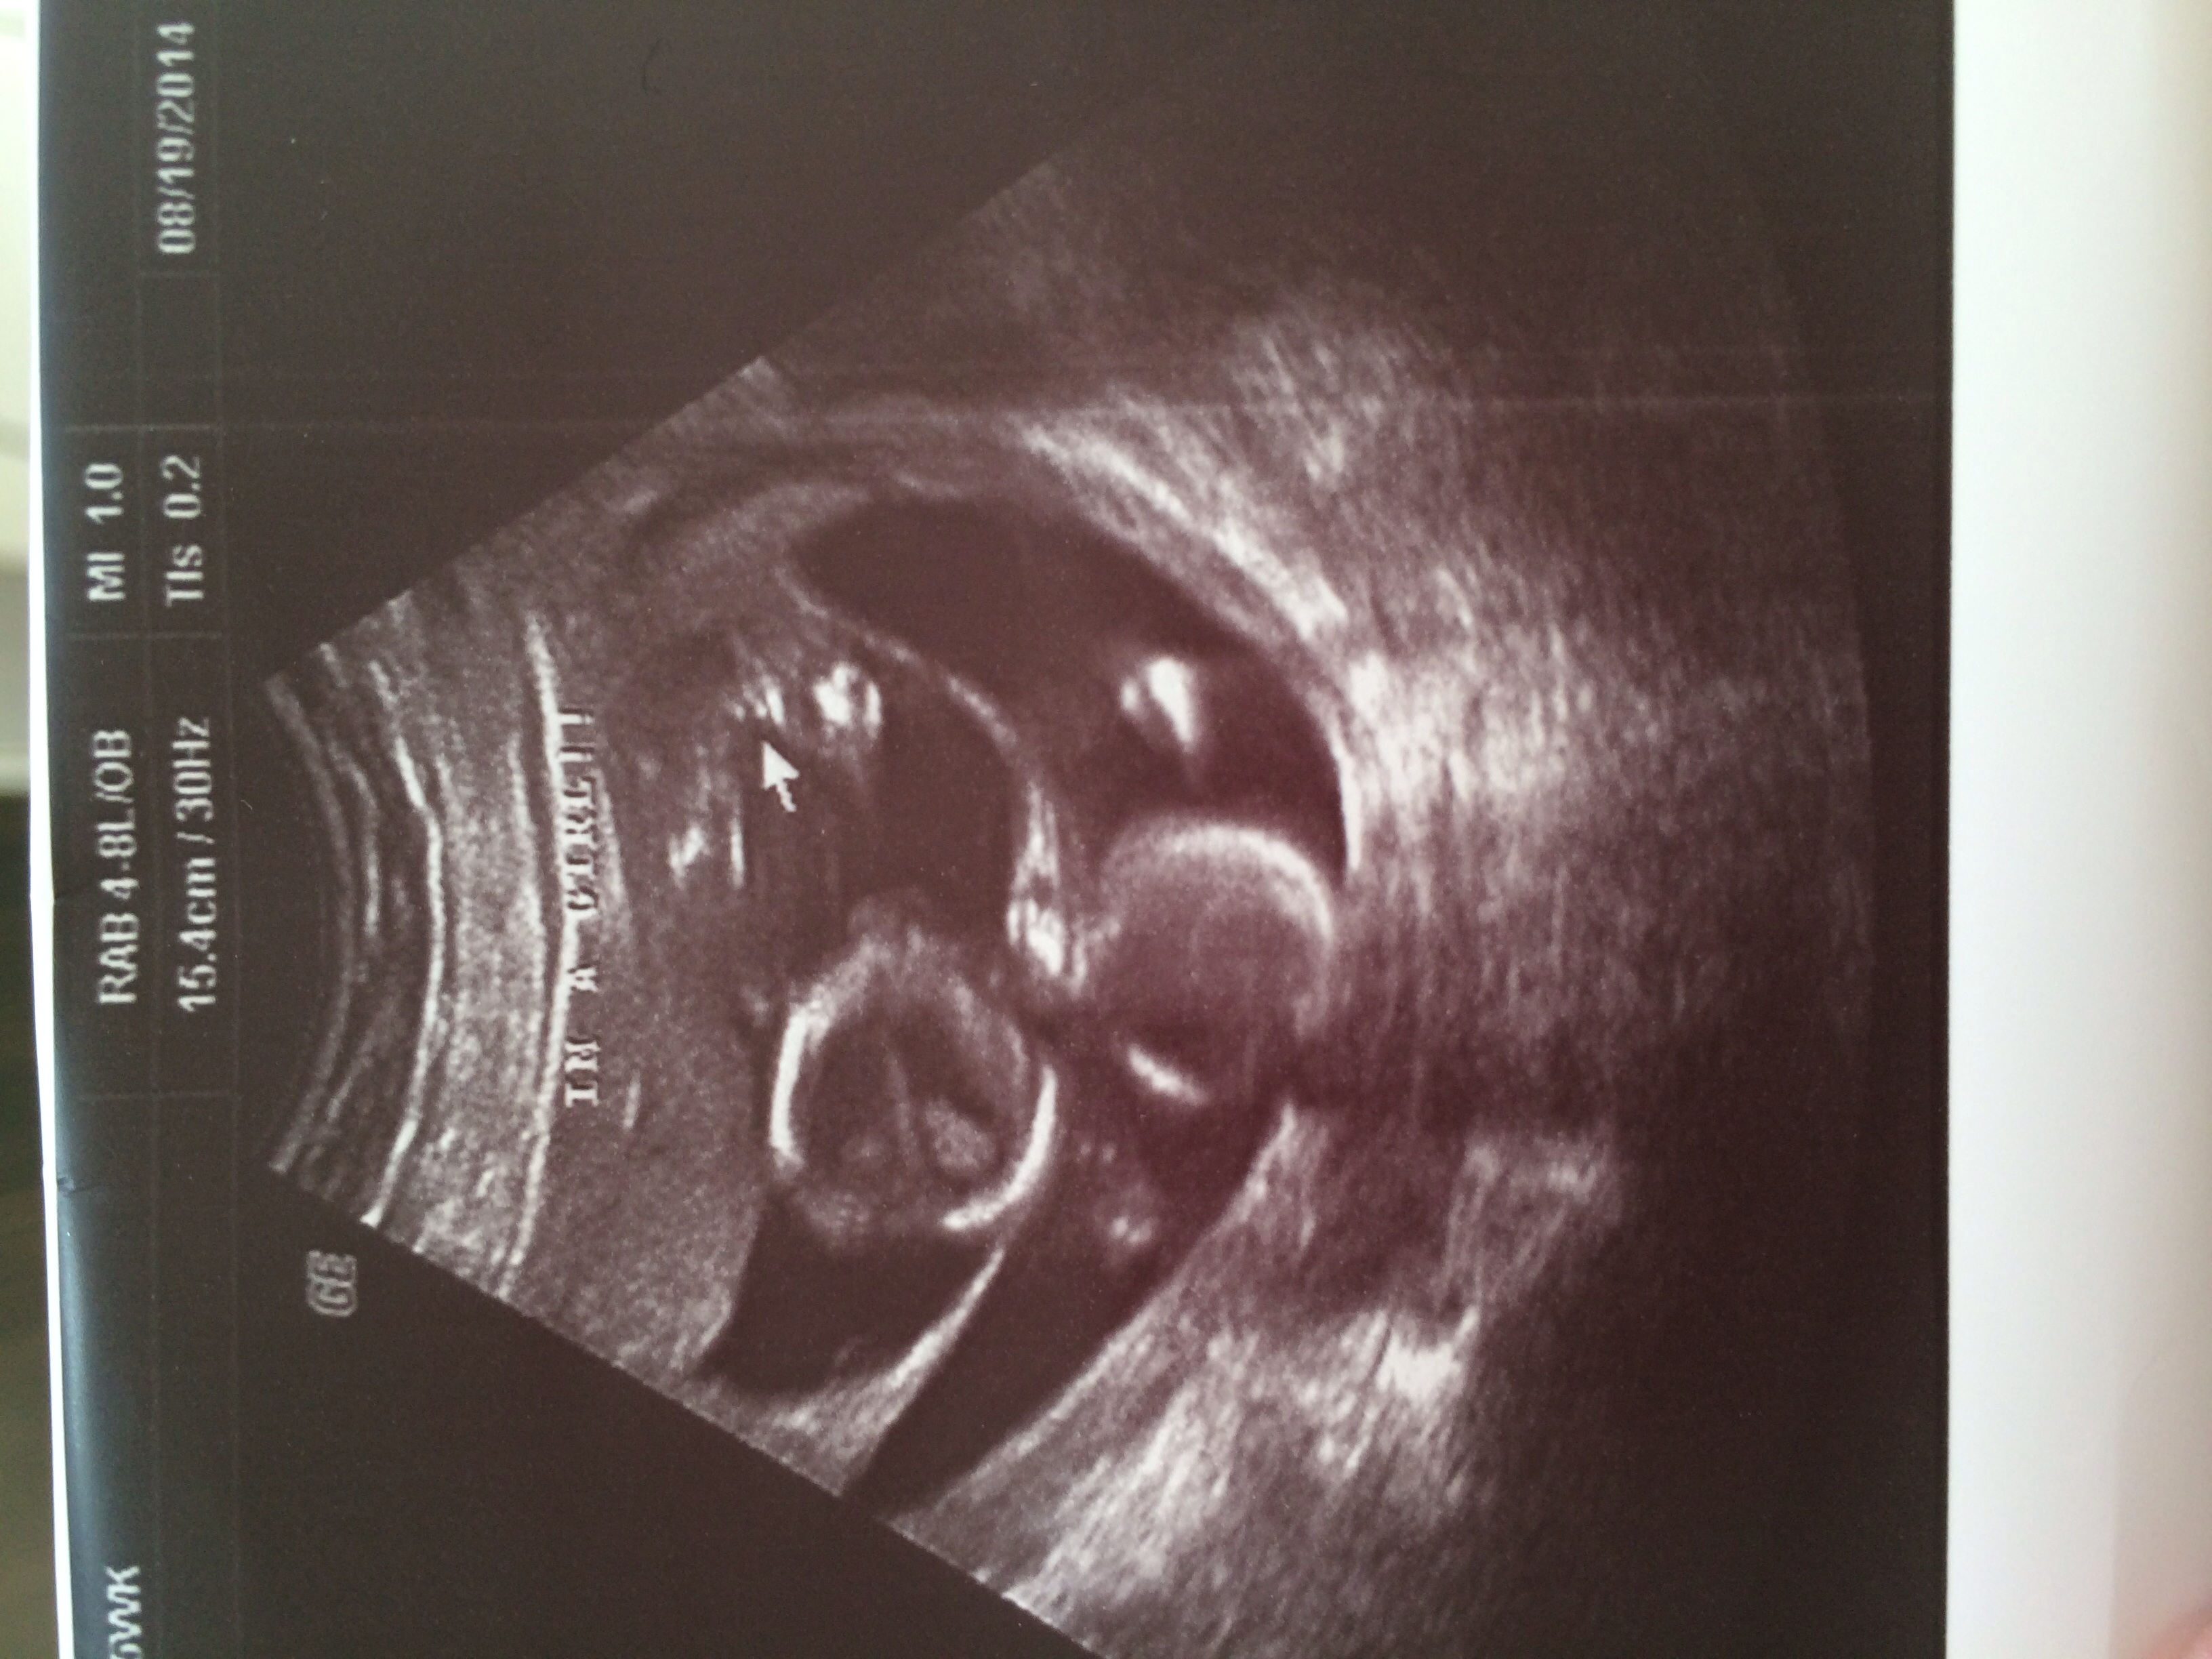

We're having 2 baby girls! U/S was today.

• @PeaceofKia‌ they're fraternal di/di twins (we did IVF)